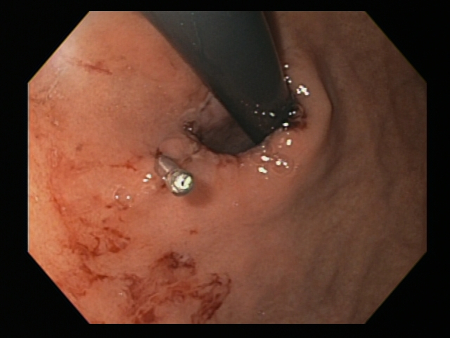

Mallory Weiss tear after application of through-the-scope clip results in haemostasis

From the personal collection of Douglas Adler; used with permission